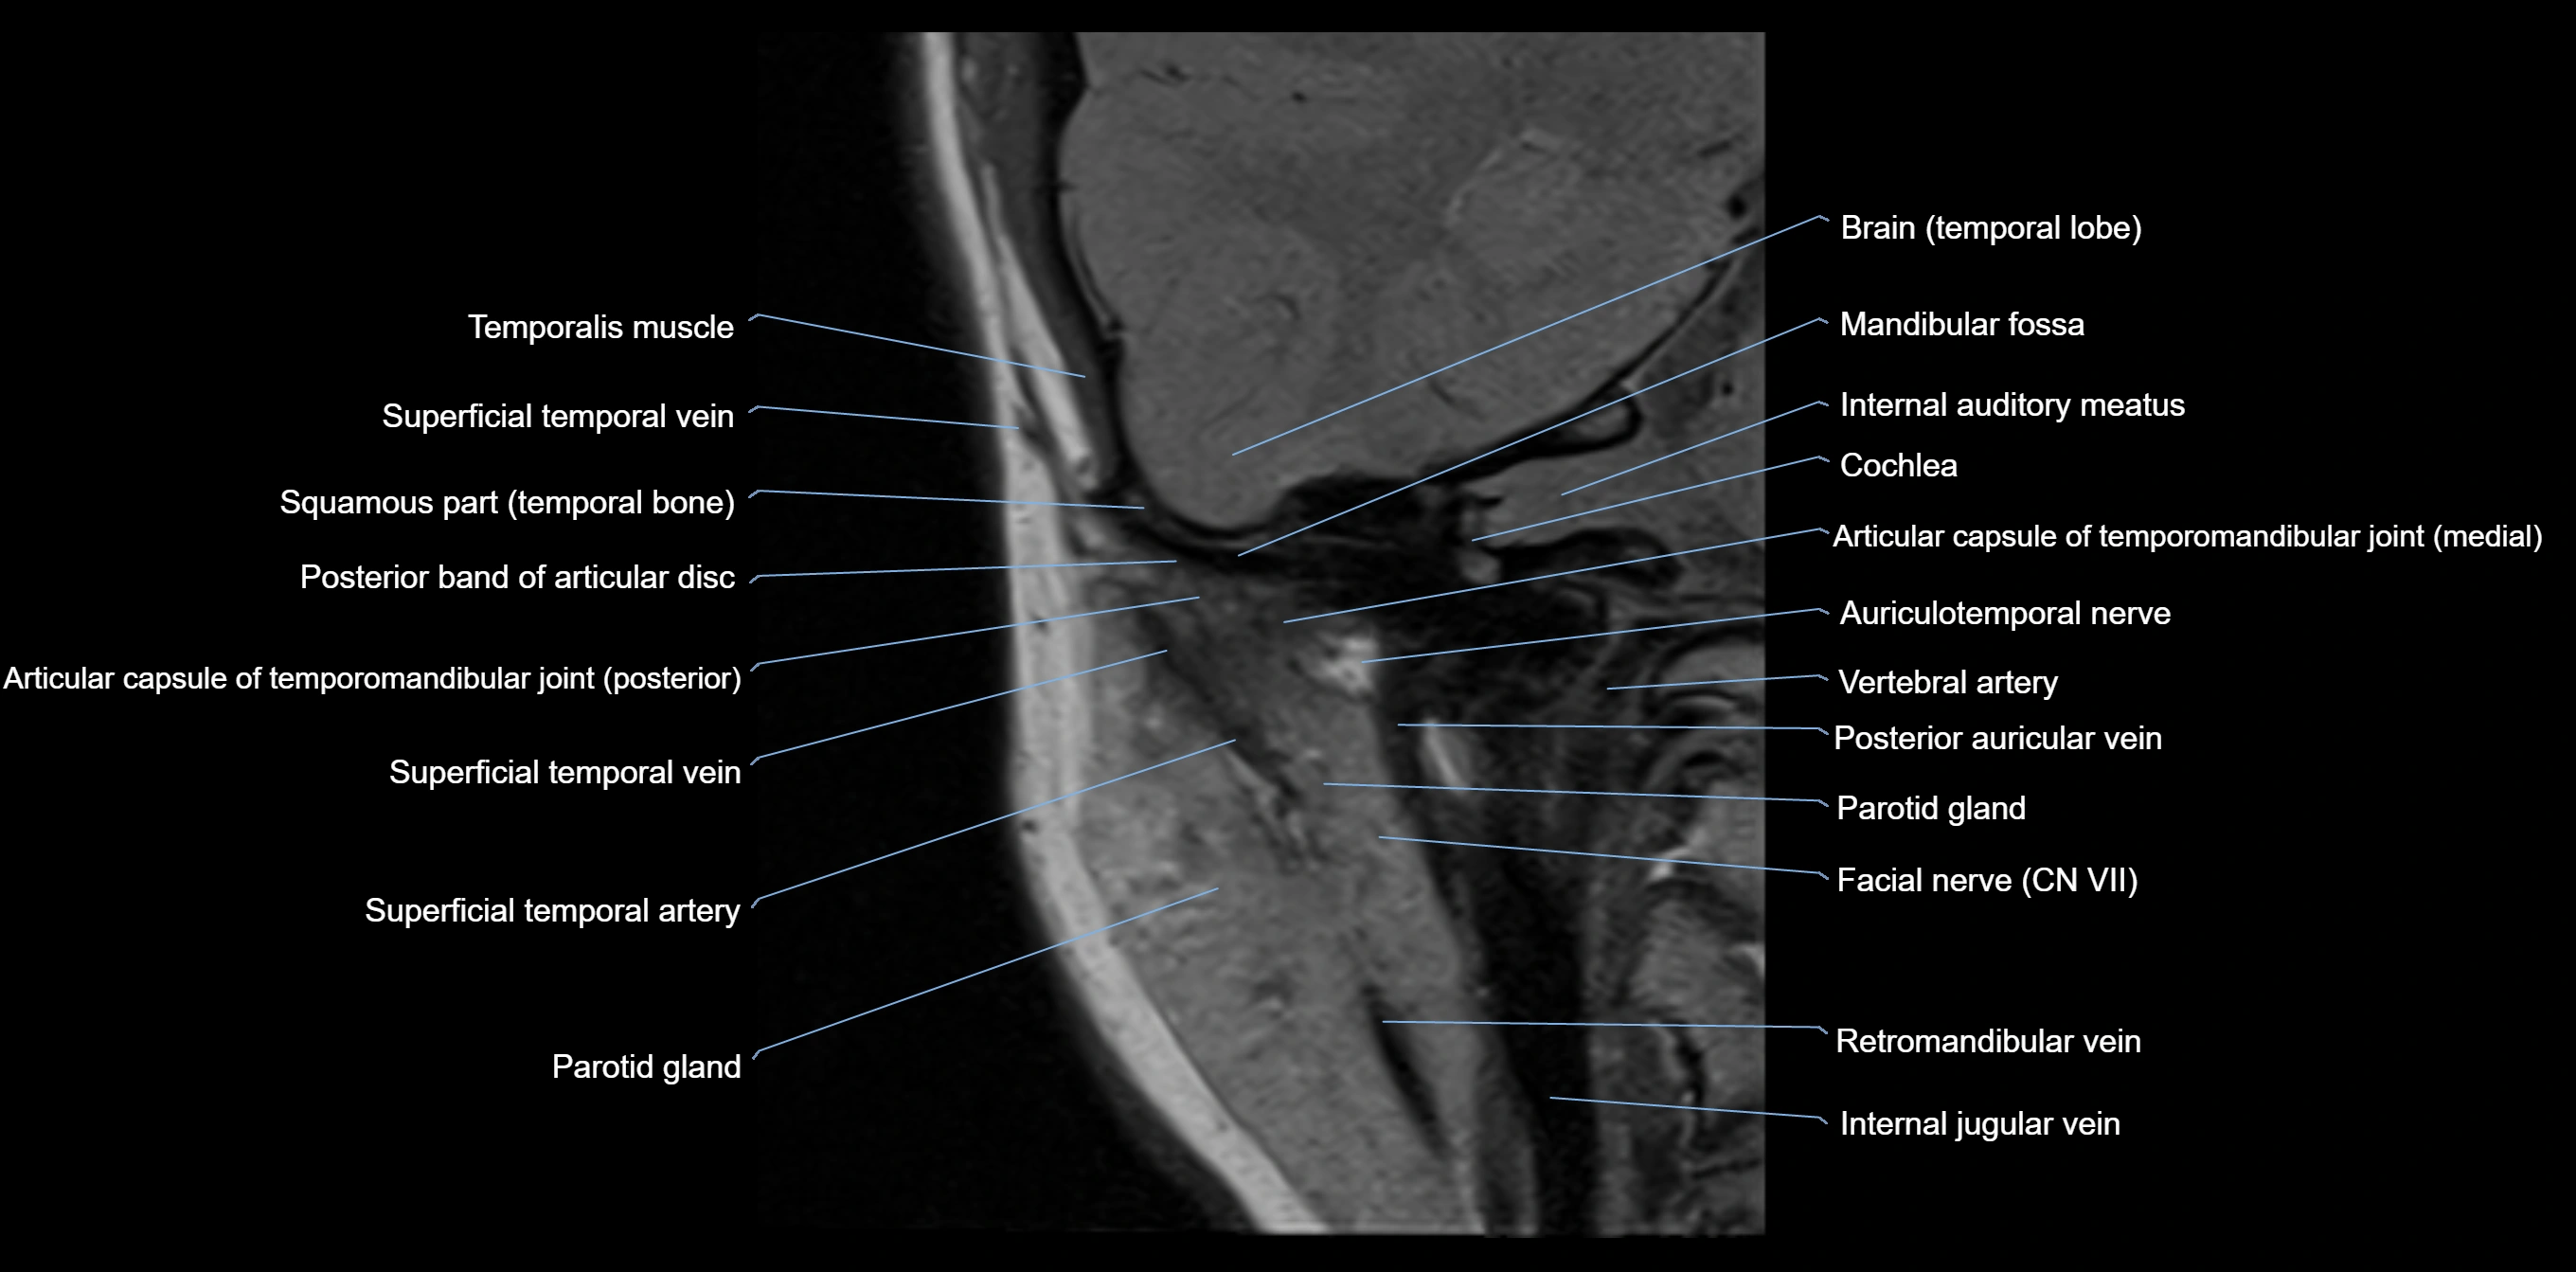

MRI appearance

T1-weighted images:

• Cortical bone: Low signal intensity

• Cancellous marrow: Intermediate to high signal depending on fatty content

• Teeth: Signal void structures

• Adjacent soft tissues: Normal gingiva and oral mucosa signal

T2-weighted images:

• Cortical bone and teeth: Low signal

• Marrow: Intermediate signal